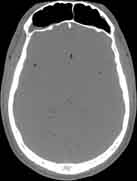

Visible Human male: Sectio transversalis 1086

CT

NMR

Pd T1 T2